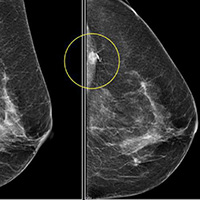

انجام آزمایش

ماموگرافی منجر به تولید تصاویر سیاه و سفید دو بعدی یا سه بعدی از بافت پستان ها

می شود. این تصاویر روی مانیتور رایانه قابل مشاهده هستند. متخصص رادیولوژی بر

اساس نتایج حاصل شده، یک گزارش نهایی از یافته های آزمایش برای پزشک شما تهیه می

کند. رادیولوژیست بر اساس تصاویر بدست آمده نسبت به وجود تومورهای سرطانی یا خوش

خیم اطمینان حاصل می کند و ممکن است برای اطمینان بیشتر ، انجام آزمایشات مجدد

دوره ای را تجویز کند. تفسیرنتایج آزمایش ماموگرافی به طور کلی ممکن است شامل موارد زیر باشد:

- وجود توده های کلیسم در غدد شیری و بافت

های دیگر پستان

- وجود توده ها و بافت های متراکم غیر

نرمال

- وجود عدم تقارن در بخش های مختلف سینه

ها

- وجود ناحیه متراکم تنها در یکی از پستان

- ایجاد یک ناحیه متراکم غیر نرمال در

مقایسه با نتایج قبلی ماموگرافی